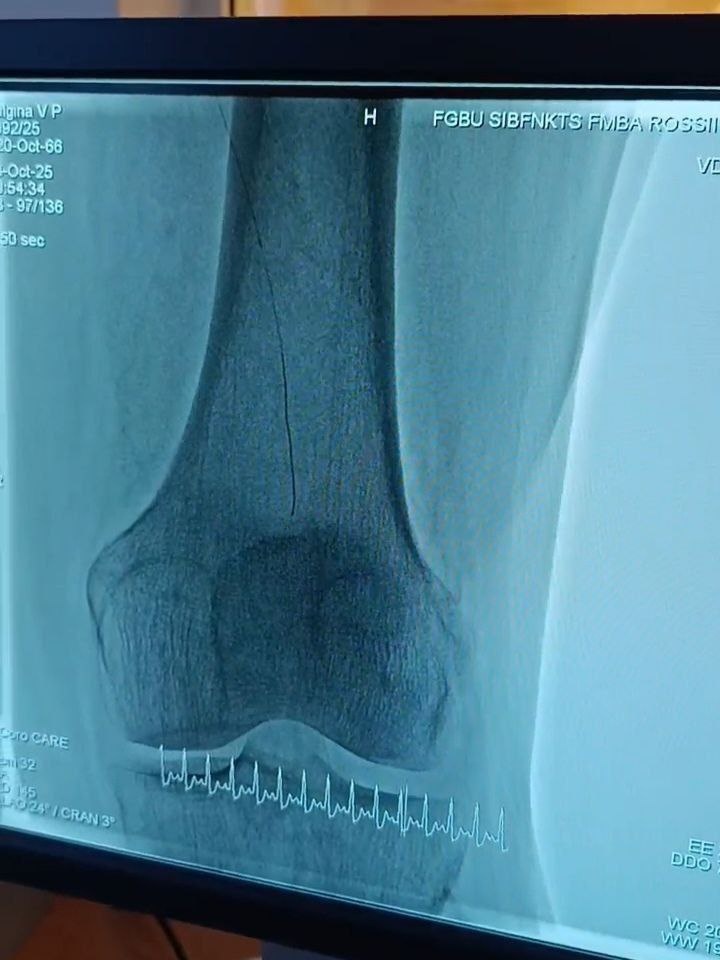

В Северске впервые провели уникальную операцию на сосудах, спасающую от ампутации В Медицинском центре №2 СибФНКЦ ФМБА России (Северск) совершили прорыв в сосудистой хирургии. 18 октября наши врачи впервые в Томской области выполнили эндоваскулярную операцию на бедренной артерии с помощью новейшего ангиографа. Пациентке с полной закупоркой артерии и риском потери конечности восстановили кровоток через крошечный прокол. Это позволило сохранить ногу и избежать тяжелой инвалидности.

В Медицинском центре №2 СибФНКЦ ФМБА России (Северск) совершили прорыв в сосудистой хирургии. 18 октября наши врачи впервые в Томской области выполнили эндоваскулярную операцию на бедренной артерии с помощью новейшего ангиографа.

Пациентке с полной закупоркой артерии и риском потери конечности восстановили кровоток через крошечный прокол. Это позволило сохранить ногу и избежать тяжелой инвалидности.